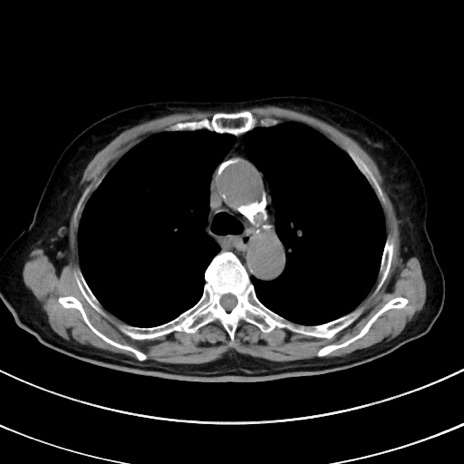

冠状断像